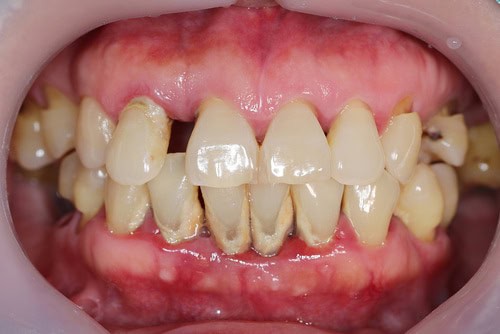

Led by one of the best cosmetic dentists in Scottsdale, Dr. Todd Shatkin has over 30 years of experience and is recognized worldwide as an innovator in the field of dentistry. He currently holds several dental-related patents, foremost being his F.I.R.S.T. technique, which allows dentists to replace missing teeth in a single office visit.

Our office is equipped with the most advanced dental technology available today including CBCT Cone-beam x-rays, intra-oral cameras, mini dental implants (using Drive Lock Technology), and the most modern dental equipment in order to provide our patients with the highest-quality, minimally invasive care with faster, more accurate results.

FADI, FICD, FICOI, DIAMDI. Member ADA, Member AGD, Fellow ICOI, Fellow ICD, Fellow ADI, Member AACD. Dr. Todd Shatkin is the co-founder of Scottsdale Dental and Facial Aesthetics in Scottsdale, Arizona. Dr. Shatkin has been in private practice in dentistry since completing dental school at the University of Pacific. Dr. Shatkin specializes in all types of cosmetic and implant dentistry, including the newest “mini dental implants”, which can be immediately “loaded” with dentures or prosthesis, to offer an immediate solution to loose fitting dentures or one or more missing teeth.